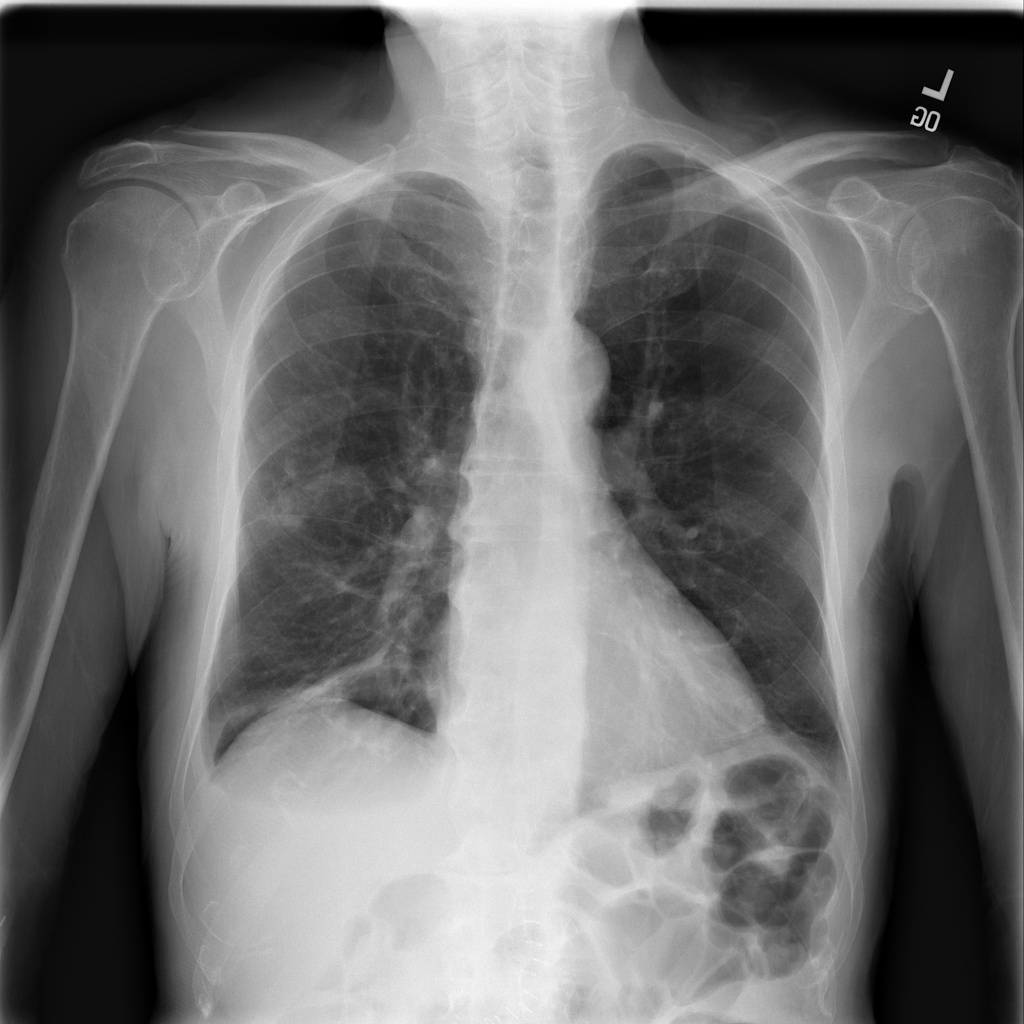

PAT-86C8 · IMG-006Atelectasis

PAT-86C8 · IMG-006

PA